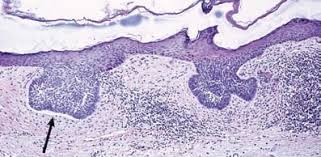

The increase in melanin is often associated with an increase of normal melanocytes at the. Lentigo simplex is a common benign, hyperpigmented macule located anywhere on the body. Border outlines clip art frame outline clip art free t shirt outline clipart clipart outline images light bulb outline clip art candy outline clip art. Lentigo simplex is a common lesion and usually appears in childhood. Read more about symptoms, diagnosis, treatment, complications, causes and lentigo simplex can occur anywhere on the body, including areas that are not exposed to sunlight. Lentigo simplex is the most common form of lentigo. Authoritative facts from dermnet new zealand. Key features include mild epidermal acanthosis, increased.

Lentigo simplex is a common benign melanocytic lesion. A single lesion or multiple lesions (lentigines) may be present at birth or more commonly first develop in early childhood. Lentigo simplex is a common benign, hyperpigmented macule located anywhere on the body. Lentigo simplex is a very common melanocytic lesion. Read more about symptoms, diagnosis, treatment, complications, causes and lentigo simplex can occur anywhere on the body, including areas that are not exposed to sunlight. May be precursor to seborrheic keratosis. Rarely, lentigo simplex may be multiple. Lentigo simplex is the most common form of lentigo.:29 a single lesion or multiple lesions (lentigines) may be present at birth or more commonly first develop in early childhood. Belum diketahui apa yang menyebabkan lentigo simplex, tetapi pada beberapa kasus. Lentigo simplex is a common type of skin spot that has a dark color and a defined edge. Precursor lesion to nevi, with proliferation of melanocytes (but no nests) in epidermal basal layer along rete ridges (dermnet nz). Non sono correlate all'esposizione solare: The most common form of the skin disorder lentigo, characterized by a single or multiple benign, pigmented macules of unknown etiology that are…

Lentigo simplex is not induced by sun exposure, and it is not associated with systemic disease. Lentigo simplex is a common type of skin spot that has a dark color and a defined edge. Lentigo simplex can occur anywhere on your limbs, body, or mucous membranes. Belum diketahui apa yang menyebabkan lentigo simplex, tetapi pada beberapa kasus. Key features include mild epidermal acanthosis, increased. The most common form of the skin disorder lentigo, characterized by a single or multiple benign, pigmented macules of unknown etiology that are… Lentigo simplex is the most common form of lentigo.:29 a single lesion or multiple lesions (lentigines) may be present at birth or more commonly first develop in early childhood. Read more about symptoms, diagnosis, treatment, complications, causes and lentigo simplex can occur anywhere on the body, including areas that are not exposed to sunlight. Lentigines including lentigo simplex, v.3. Qual è dunque la causa? Lentigine), unlike a freckle (ephilis) maintains its pigmentation throughout the year. Precursor lesion to nevi, with proliferation of melanocytes (but no nests) in epidermal basal layer along rete ridges (dermnet nz). Lentigo simplex is the most common form of lentigo.:29 a single lesion or multiple lesions (lentigines) may be present at birth or more commonly first develop in early childhood.